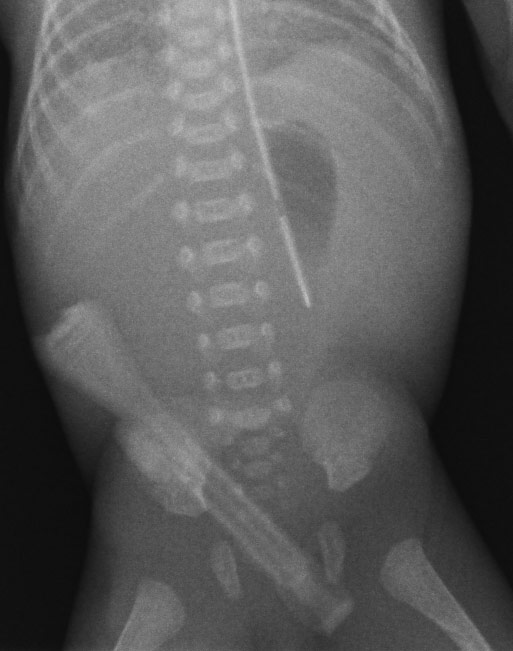

智能降噪利用深度卷积神经网络技术,提供卓越的基于 CNN 的噪声消除,产生更出色的影像质量,保留细腻细节,实现更好的对比噪声比以及易读的 X 光照片。